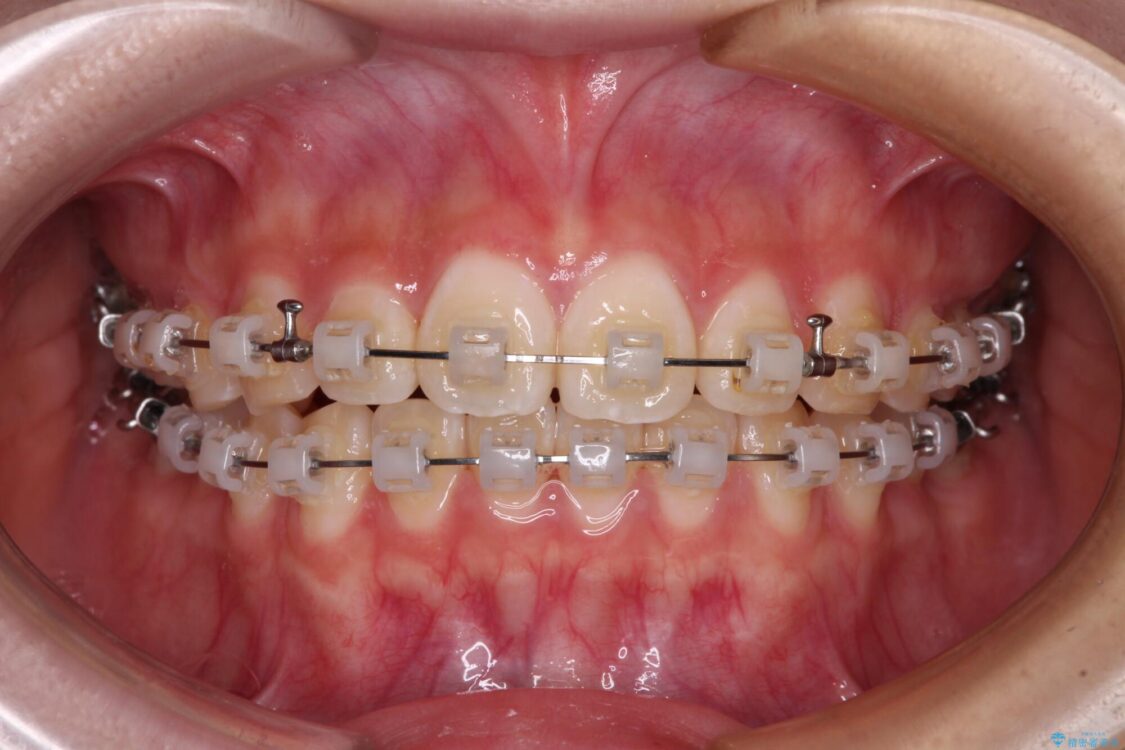

治療途中

• インビザラインは使える自信がない ワイヤー装置にて矯正治療 治療途中画像